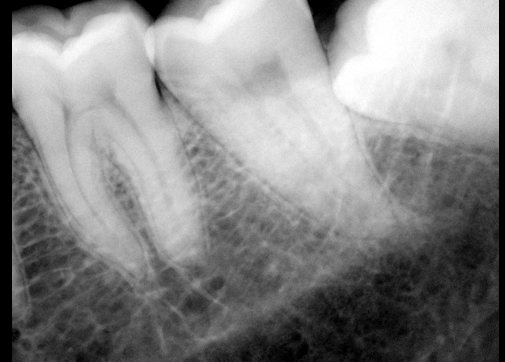

CR/DR 牙齿分割阶段记录

当前进展

- 完成了 CR/DR 牙齿相关分割训练

相关测试

遇到的问题

- 训练过程中出现过 mask 下移问题

- 部分结果会出现 box 填充异常

- mask 边缘仍然有比较明显的锯齿感

参考